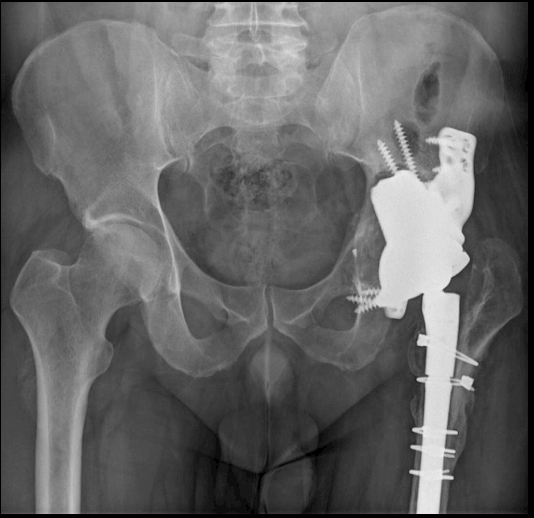

Acetabular replacement, 2015. Last follow-up at the previous center.

First visit to Hospital Parc Taulí (2021):

- Change of treatment center

- No pain. Proper function

- Age: 47 years